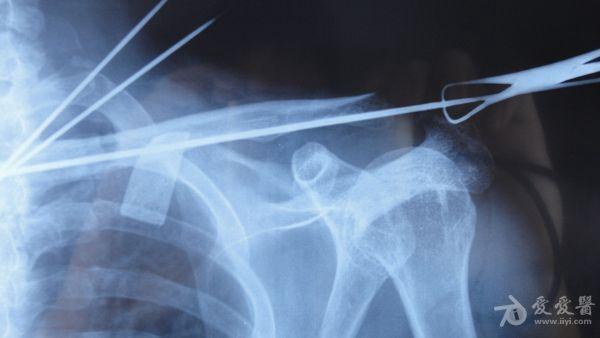

患者**,男,43岁,2个月前因不慎摔伤致左锁骨内侧骨折,行保守治疗,锁骨、前臂吊带固定。定期拍片复查,最近一次X片示骨折断端内侧向后上移位,外侧向前下移位。于12月20日诊断以“左锁骨骨折骨不连2月余”入院。专科检查:左锁骨压痛叩击痛,外形畸形,肩关节活动受限。昨日在臂丛下行骨折切开复位内固定术,用三枚克氏针固定。大家看一下,讨论讨论有什么更好的办法吗?受伤时

术中照片